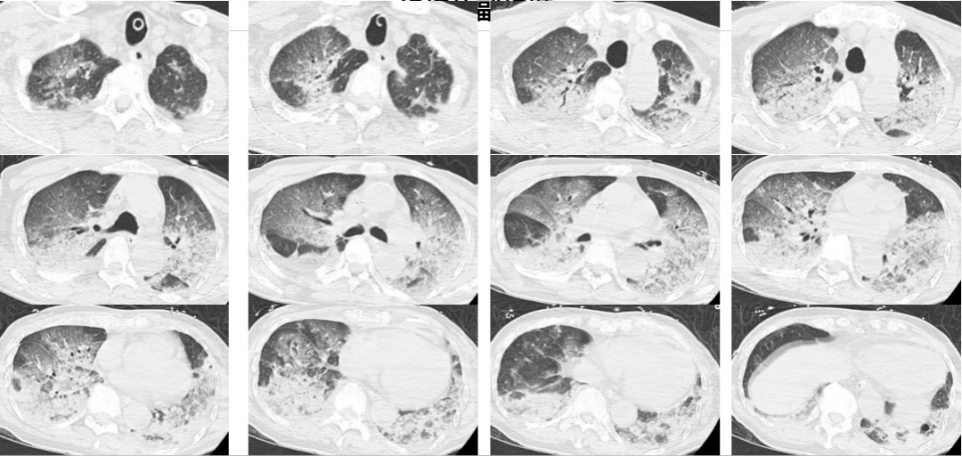

入院时,韩爷爷意识不清,血压、心率下降,医生随即为他安排头颅、胸部CT和肺血管CTA检查,结果显示,老人的双肺出现大面积白色影像。经会诊,韩爷爷被确诊为热射病诱发的肺水肿。